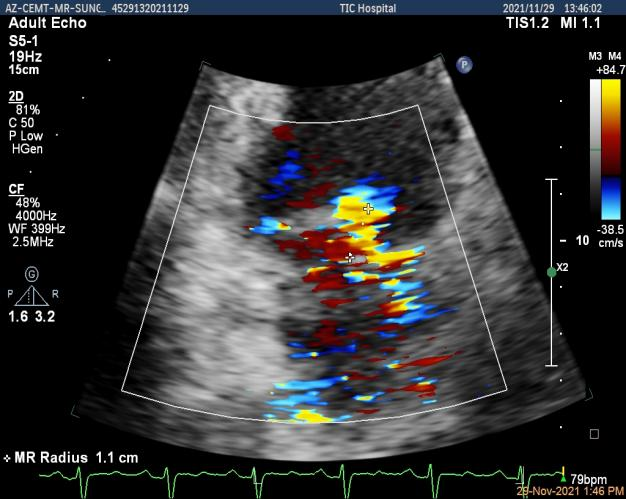

3D-color MV view:大量反流,起源于1区